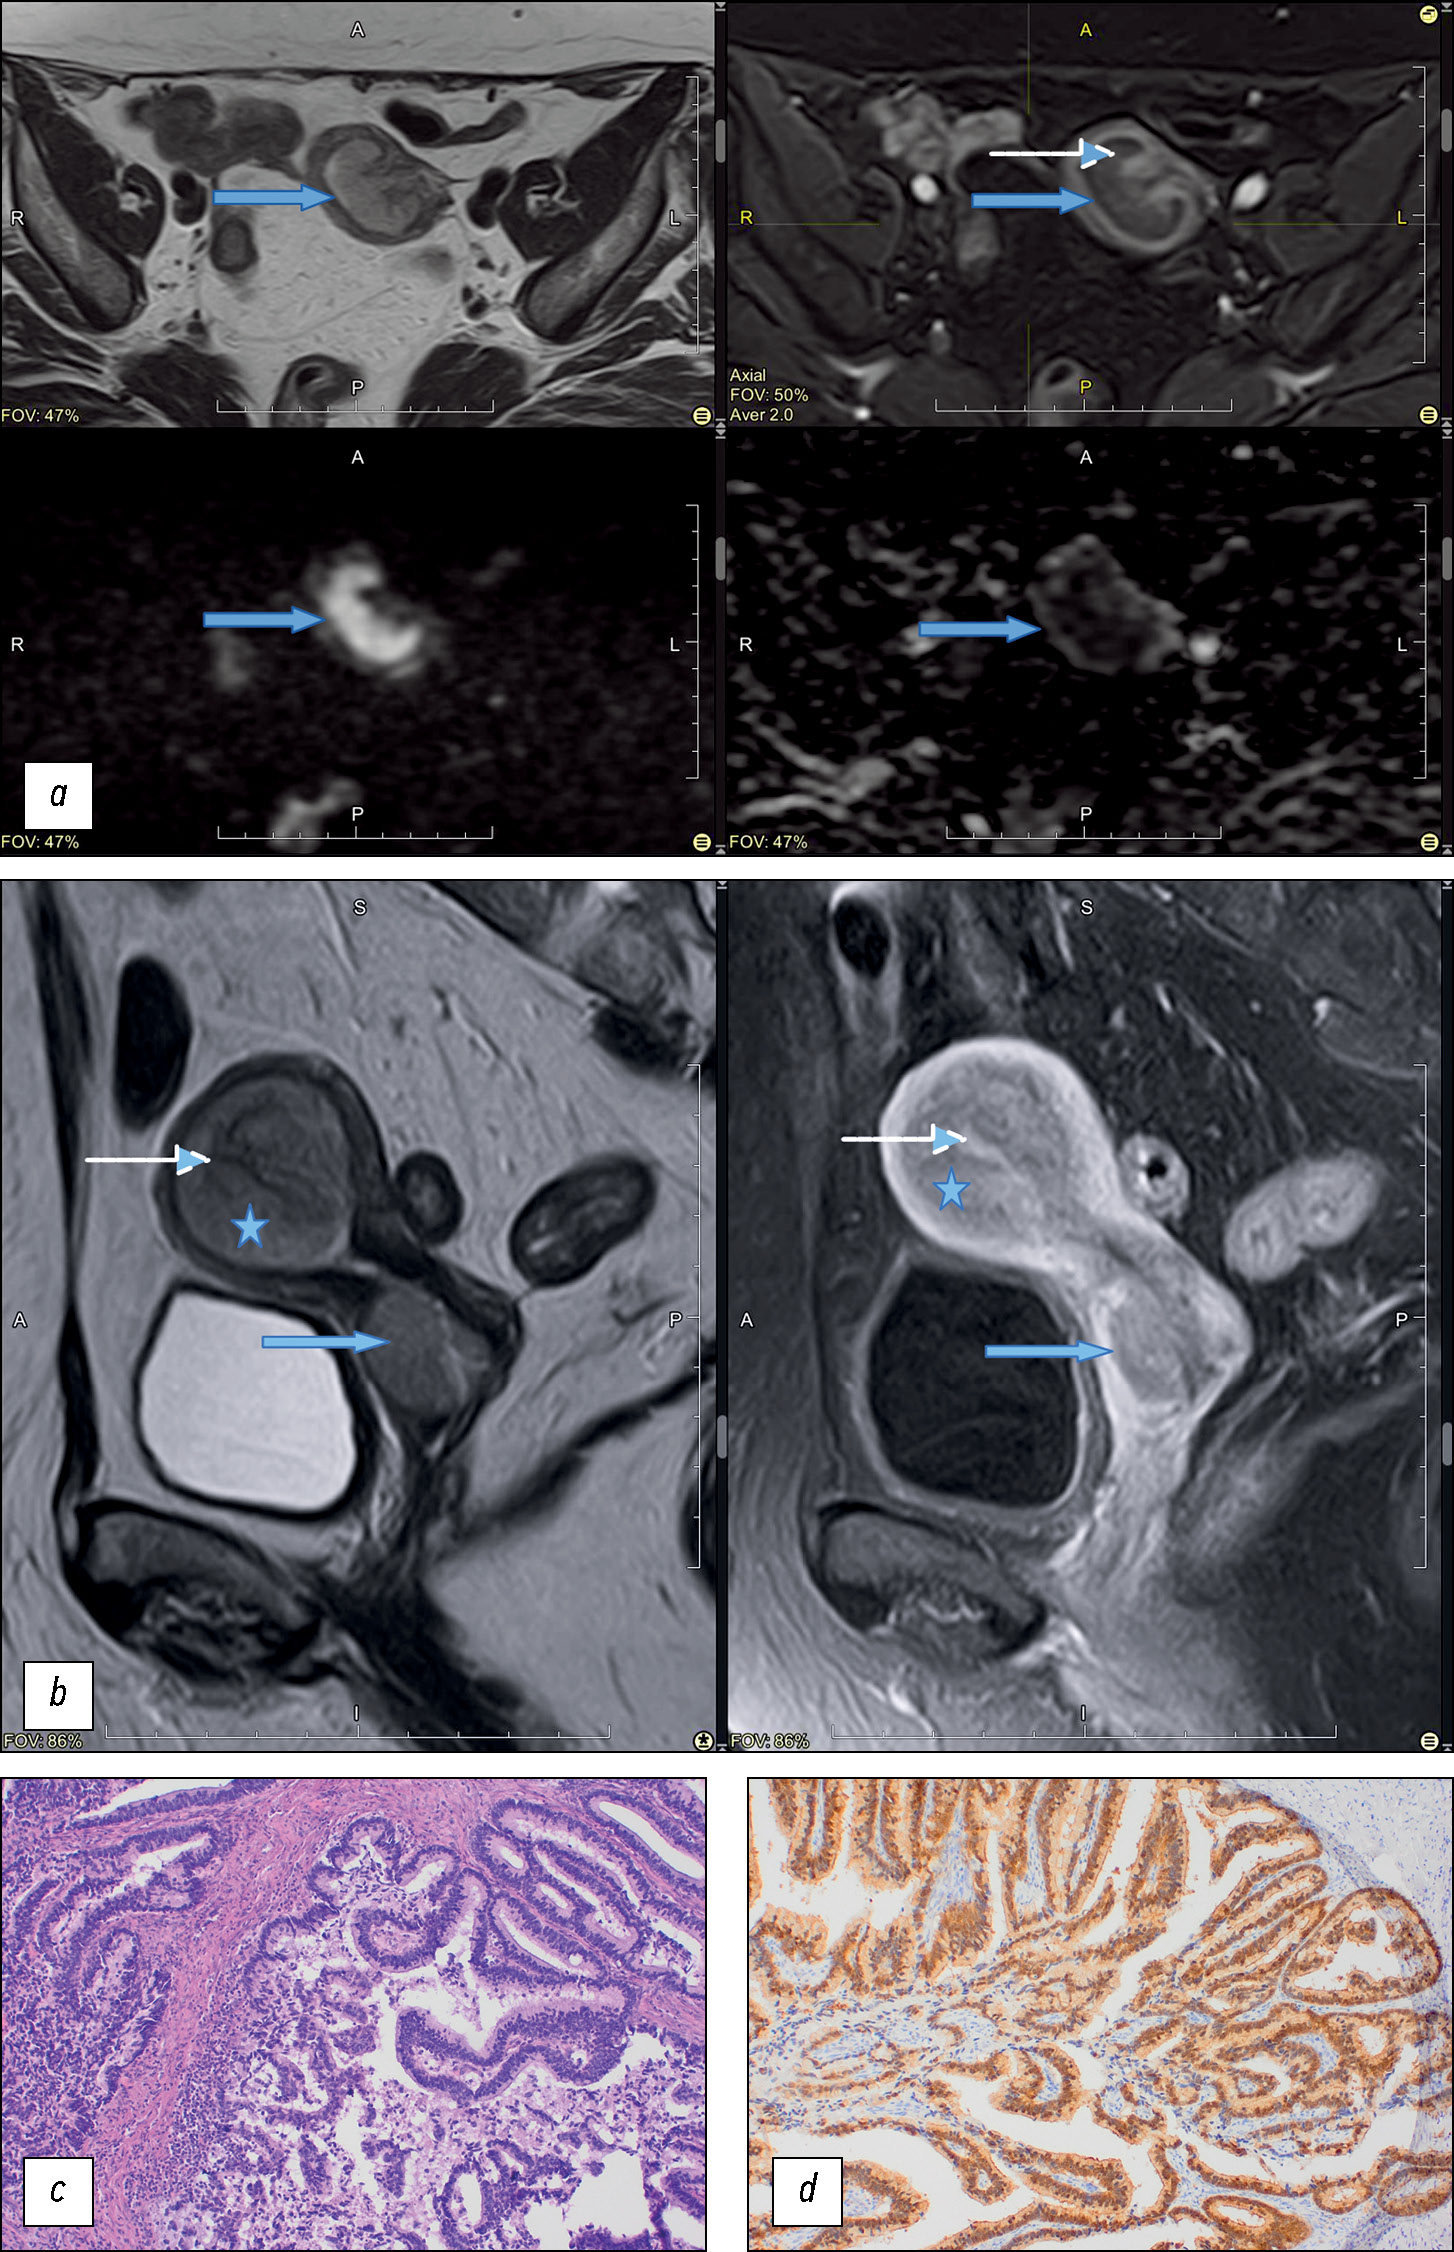

The locally invasive growth pattern with tumor pedicle formation was observed, and feeding vessels were visualized (41%) in the endometrial CA seeding lesions (Fig. 5).

Fig. 5. Magnetic resonance imaging of the pelvis (cervical adenocarcinoma), metastasis in endometrium:

(a) from left to right and from top to bottom: T2-weighted image, T1FS-weighted image with contrast enhancement in the arterial phase, diffusion-weighted imaging (DWI), and apparent diffusion coefficient (ADC) map. The tumor (metastasis in endometrium) is marked with an arrow. The region of the “leg” of the tumor and feeding vessels are marked with a dotted arrow; (b) sagittal plane, T2-weighted image (left) and T1FS+C (right): primary tumor (arrow), metastasis in the body of the uterus (star), vessels in the focus of tumor (dotted arrow). In the arterial phase of DСE, the accumulation of paramagnetic by the basal layer of the endometrium and the vessels in the “feeding leg” of the tumor is determined; (c) histological examination of the surgical material, stained with hematoxylin and eosin, ×10; d, immunohistochemical study, expression of p16.

Conclusion of the pathomorphological study: Moderately differentiated endocervical adenocarcinoma. The tumor grows into the stroma of the cervix to a depth of 1.3 cm (2/3 of the thickness of the wall of the cervix in the transition zone). The tumor grows into the myometrium (to a depth of 0.6 cm, 1/3 of the thickness of the uterine body wall) and endometrium. The vaginal part of the cervix is covered with a multilayer flat epithelium.